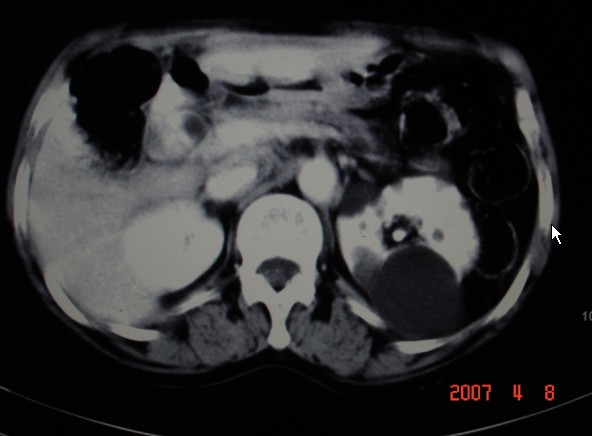

以下是引用dyqct在2007-4-9 10:45:00的发言:[br]考虑:1、肝门区占位性病变(以胆管癌可能性大伴肝内胆管轻度扩张);[br] 2、左肾多发囊肿。

以下是引用zsl6918在2007-4-9 9:18:00的发言:[br]薄层处理一下肝门部会发现病灶,应该是比较典型的肝门部胆管细胞癌,左肾囊肿。在机器上看会更清晰。

以下是引用狙击手在2007-4-9 9:31:00的发言:[br]从走形及位置看像是扩张的肝右管,增强后见周围有明显比正常肝组织强化程度高的环形组织影,考虑肝门部胆管细胞癌可能性大;左肾囊肿。

以下是引用卜一在2007-4-9 10:33:00的发言:[br]1 胆管细胞癌。[br]2 左肾囊肿。[br]支持!

以下是引用qiuleiyu在2007-4-9 12:14:00的发言:[br]支持肝门部胆管细胞癌,左肾囊肿。左肾上腺区转移?胆囊显示不清,请结合临床。